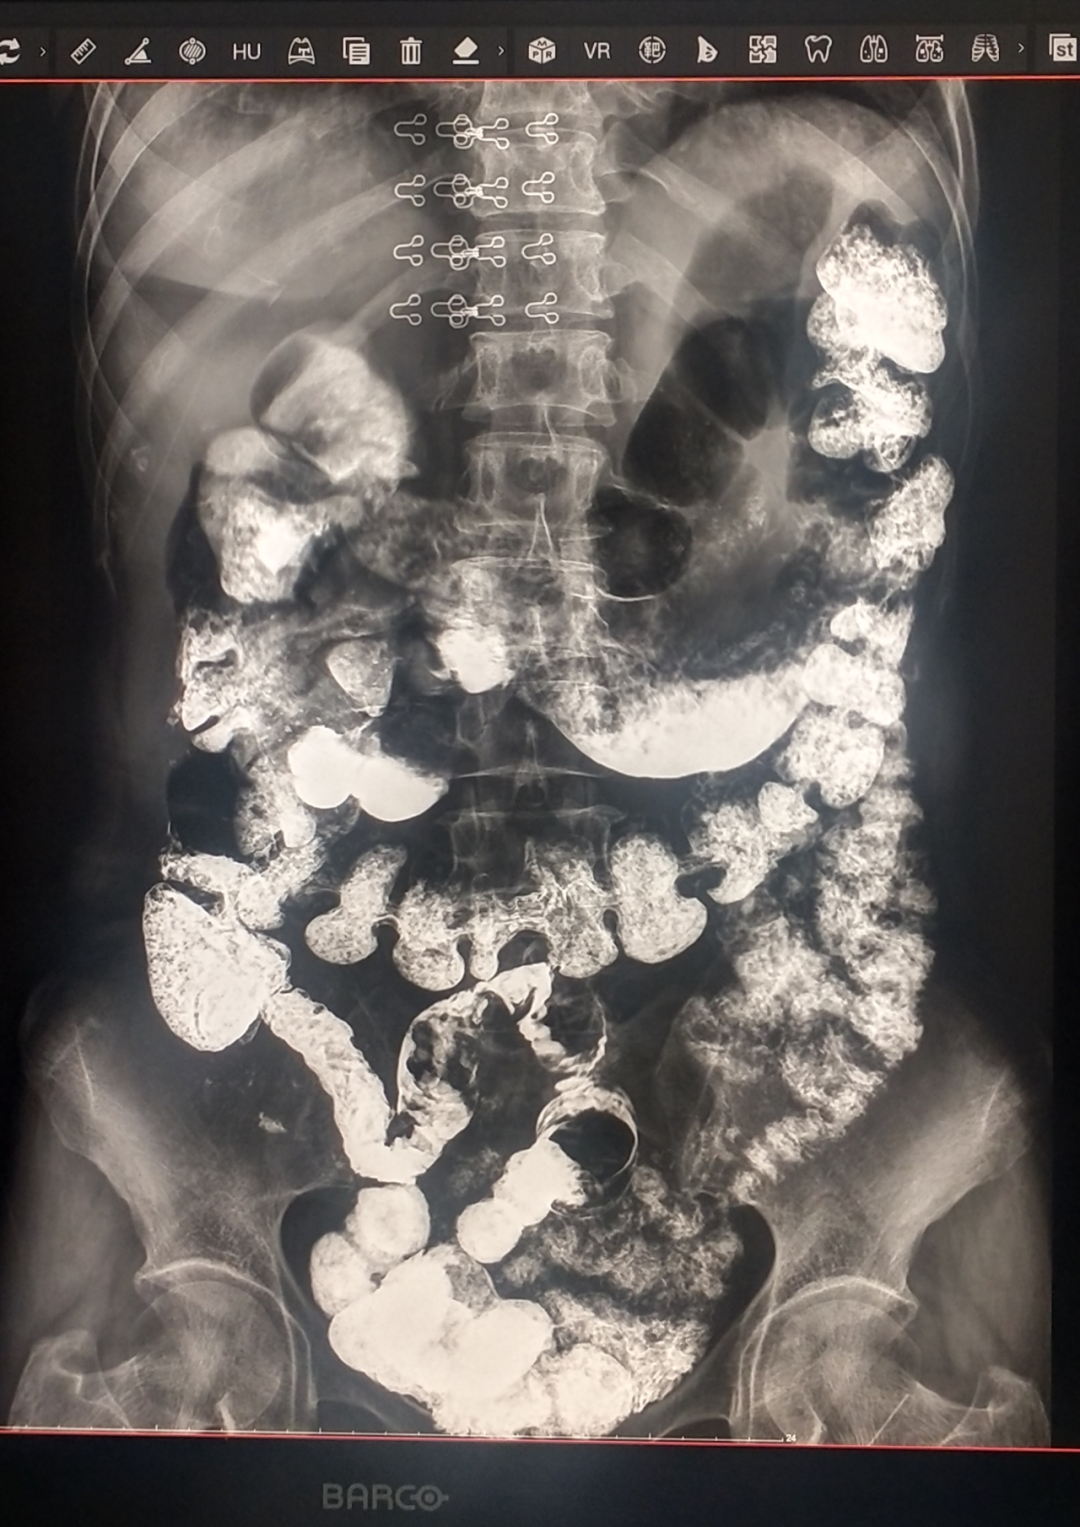

“胃”雨綢繆,“腸”享人生——酒泉市中醫(yī)醫(yī)院放射科開展X線胃腸造影檢查

醫(yī)生:既然你真心誠意的發(fā)問了,那我就開始上技術(shù)了。這個“白糊糊”叫做硫酸鋇,是消化道造影檢查的造影劑,不溶于水和脂肪,不被腸粘膜吸收,對人體無害,喝了它后在X射線照射下能顯示消化道病變,我們將以各種角度在這個機器上檢查。然后,消化道會以這樣的形式和我們面對面。

醫(yī)生:消化道造影檢查可以觀察胃腸道黏膜、輪廓、蠕動及通暢性,反映消化道某些病變范圍及性質(zhì),如先天畸形、炎癥、息肉、腫瘤、潰瘍等。

醫(yī)生:為了給廣大患者提供更精準、更舒適、更高效的醫(yī)療服務(wù),酒泉市中醫(yī)醫(yī)院院放射科引進了最先進的數(shù)字胃腸設(shè)備,這一重大舉措標志著我院在胃腸道疾病的診斷和治療方面又邁上了一個新的臺階,為胃腸道疾病的診斷打開了全新的視角,通過多維度、動態(tài)化的成像,醫(yī)生能夠全方位、實時地觀察胃腸道的蠕動、排空等功能狀態(tài),對功能性胃腸疾病的評估更加精準。而且,檢查過程更加快捷,減少了患者的等待時間和不適感,讓您在更短的時間內(nèi)獲得更可靠的診斷結(jié)果,為大家的胃腸道保駕護航。